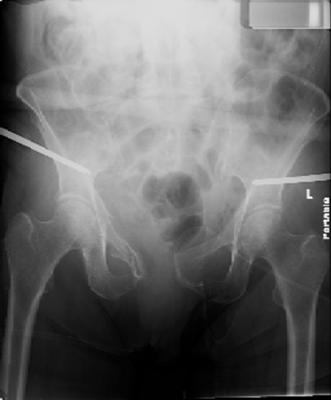

attached are images of a 70 year old female after peds versus car. her own car ran her over.

injuries are limited to the pelvis. left rami open and visible in a 10cm vertical laceration just lateral to left labia majora. wound is grossly clean. no vaginal and no urinary issues. CT scan shows widening of both SI joints anteriorly but I think this is vertically stable pattern.

pt treated that night with I/D and supra-acetabular frame to close the ring. consideration was given for SI screws bilateraly, but given time of night and other factors decision made not to proceed.

so the question is what next operatively if anything? concerns are infection, nonunion anteriorly and possible incompetence of the pelvic floor which may lead to prolapse issues. right rami are comminuted and plating may entail ilioinguinal approach to extend plate laterally to right iliac wing. retrograde screw up right rami is an option but I am not convinced it will add much. adding SI screws very doable, but major concern is restoring anterior ring. so far wound is clean and closed over a drain, and I have no plans to open it back up and wash again.

maintaining pelvic alignment in ex-fix in 70 yo female for any length of time may be challenging.

any thoughts? would anyone plate the pubic symphysis to close the gap and leave the more lateral rami fractures alone? the most recent pelvic case on this website involved pts with suprapubic catheters and antibiotic options including resorbable beads. I wonder how many people would plate and place antibiotic beads. thanks.